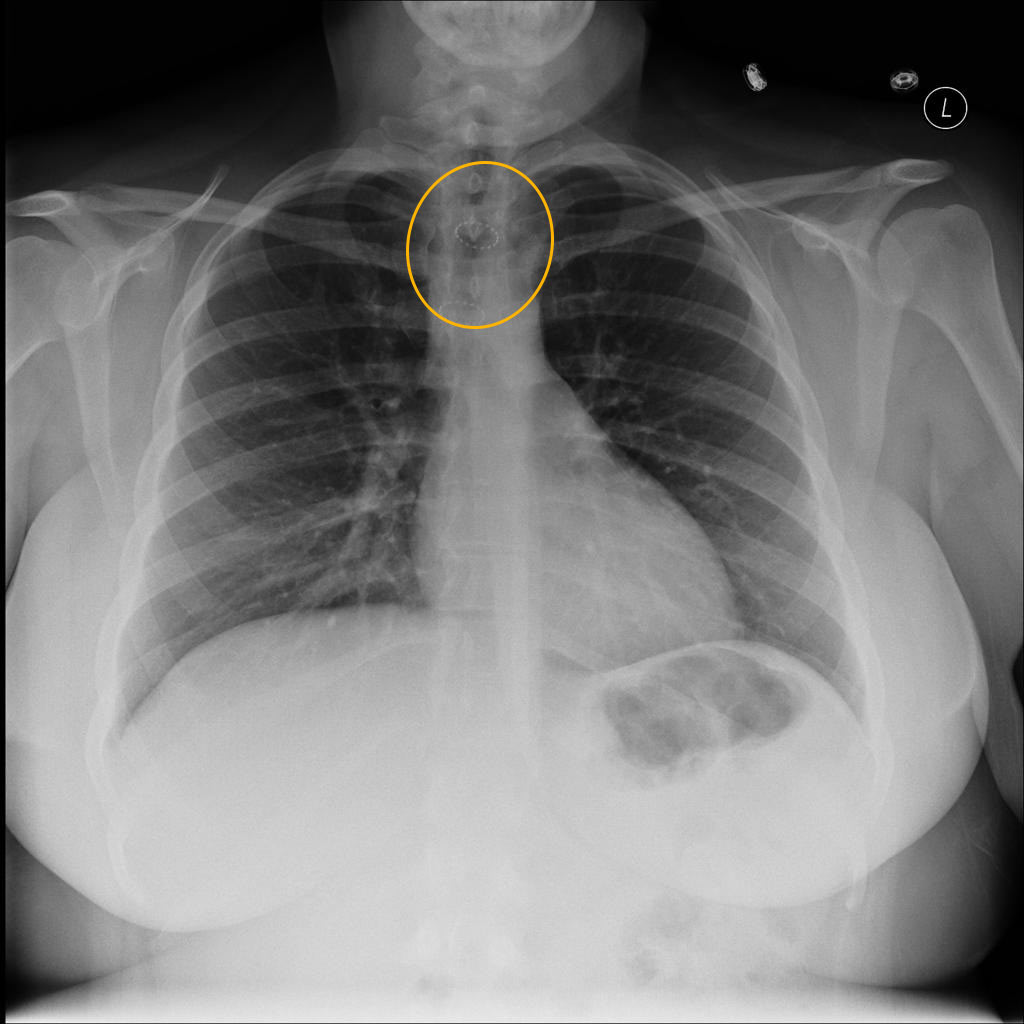

Os sinais clínicos já são indicativos da estenose traqueal, mas o diagnóstico correto da doença é feito através de tomografias computadorizadas e broncoscopias.

Imagens endoscópicas de Ressecção por laser de estenose traqueal, a primeira ressecando e a segunda aspecto final, com a luz traqueal totalmente aberta.